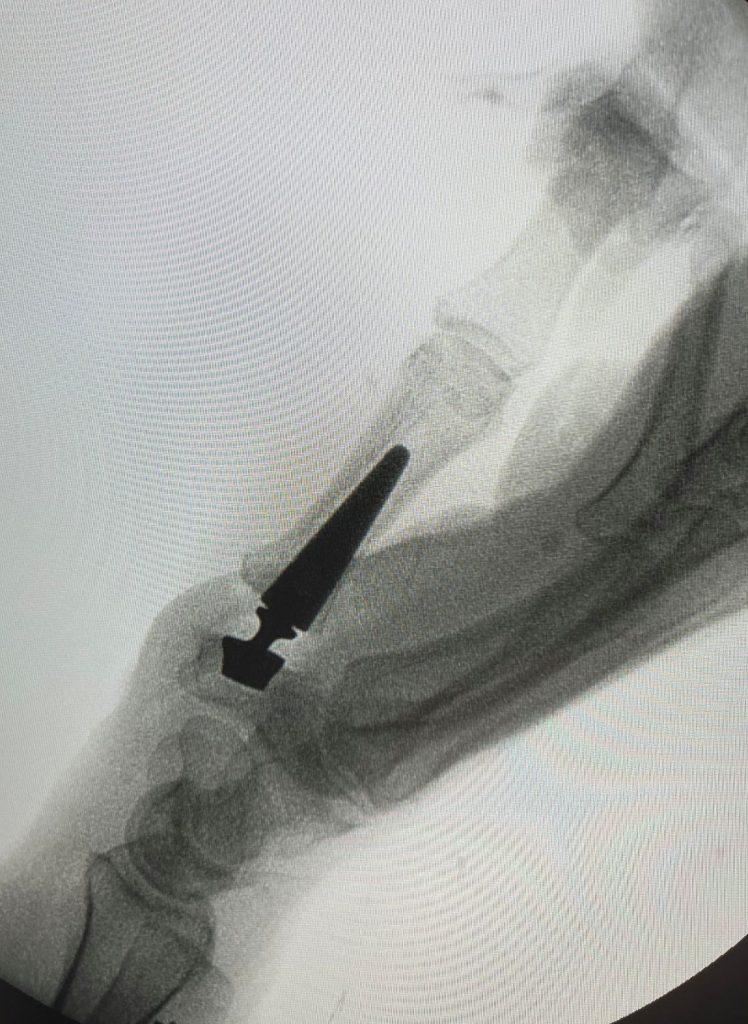

RIZARTROSIS Figura 3 - Prótesis de articulación TMC por rizartrosis AP

Figura 3 - Prótesis de articulación TMC por rizartrosis AP

RIZARTROSIS Figura 4 - Prótesis de articulación TMC por rizartrosis LAT

Figura 4 - Prótesis de articulación TMC por rizartrosis LAT